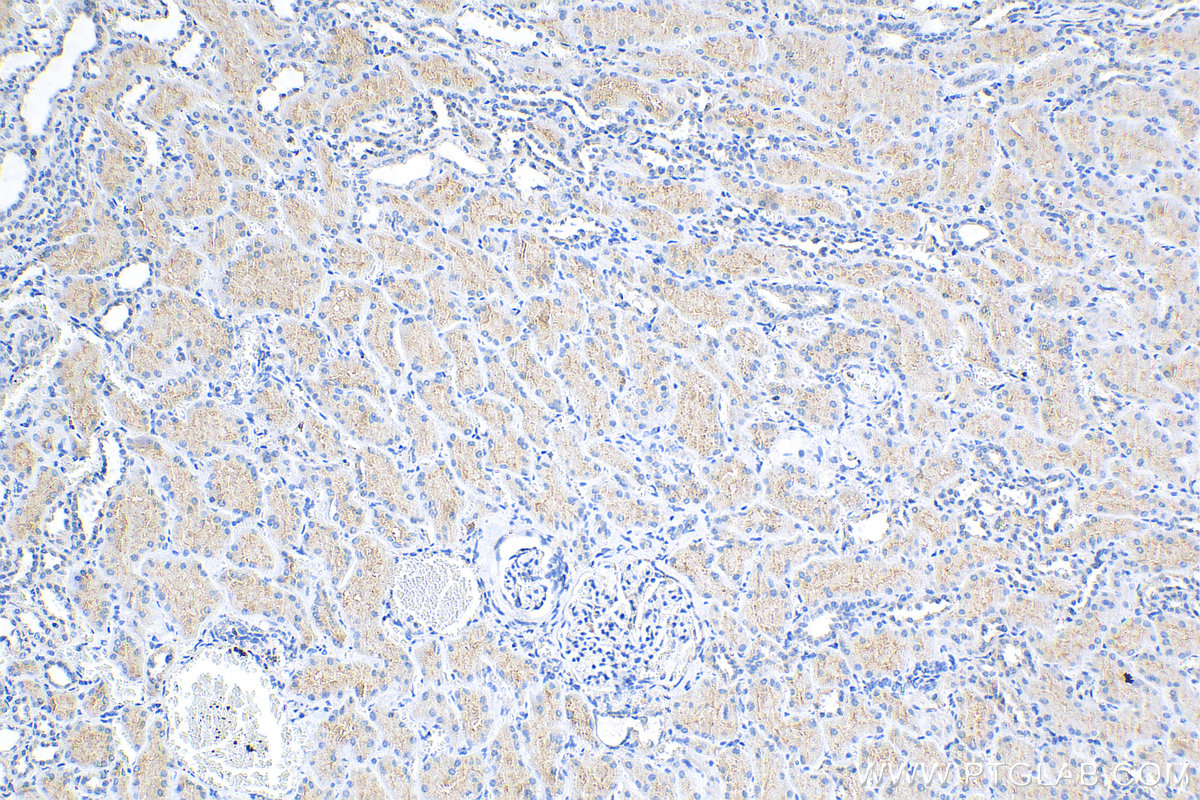

| Positive IHC detected in | mouse kidney tissue, human kidney tissue,  mouse brain tissue,  rat kidney tissue Note: suggested antigen retrieval with TE buffer pH 9.0; (*) Alternatively, antigen retrieval may be performed with citrate buffer pH 6.0 |

| Immunohistochemistry (IHC) | IHC : 1:300-1:1200 |